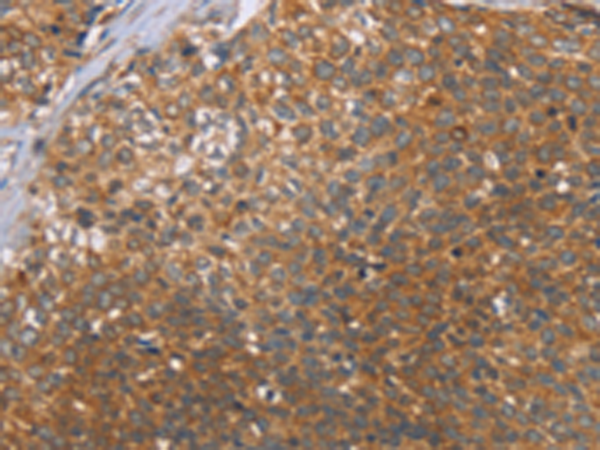

分类: 科研抗体货号: P07154别名: Car3; CAIII应用: WB,IHC反应种属: Human, Mouse, Rat